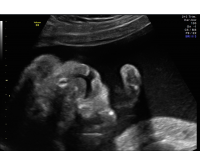

Cleft lip/palate is typically identified in the second trimester of pregnancy using ultrasound. Additional imaging, such as 3D ultrasound and MRI, can allow for better visualization of the palate. As clefting is frequently associated with additional abnormalities and genetic syndromes, including chromosome abnormalities, genetic counseling and testing (such as amniocentesis) are offered. Consultations with neonatology and specialty surgeons are recommended to discuss prognosis and management options after birth.

Cleft lip 3D